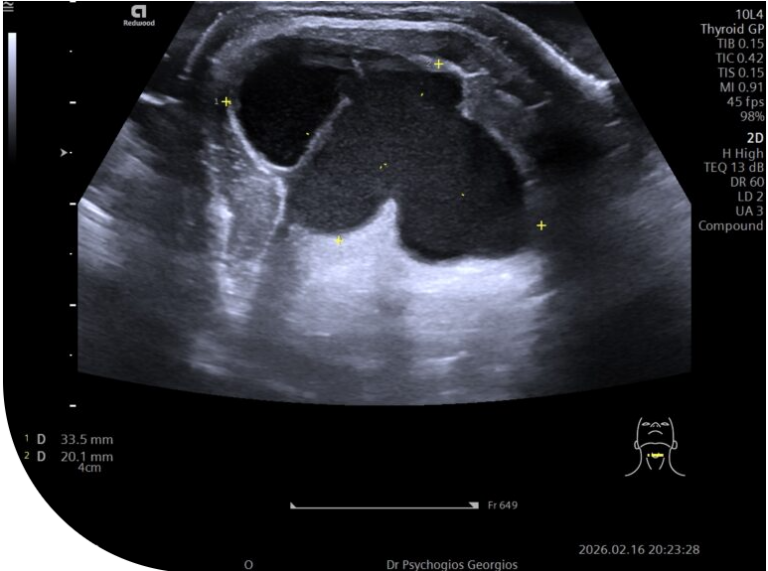

Εγκάρσια υπερηχογραφική απεικόνιση ευμεγέθους κύστης θυρεογλωσσικού πόρου